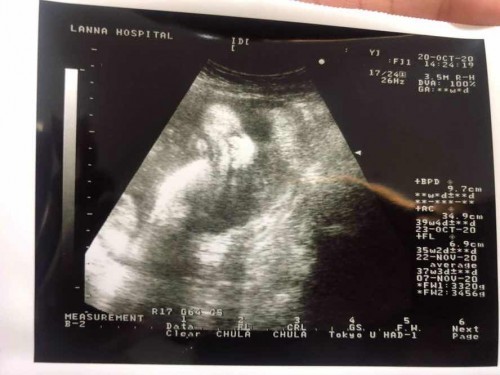

บ้านนี้ 38+4 วีค น้องน้ำหนัก 3,300 g แล้วจ้า น้องกำลังเพิ่มน้ำหนักเองในท้องแม่ 😅 แม่ๆบ้านอื่นตัวเล็กหนักเท่าไหร่กันแล้วคะ